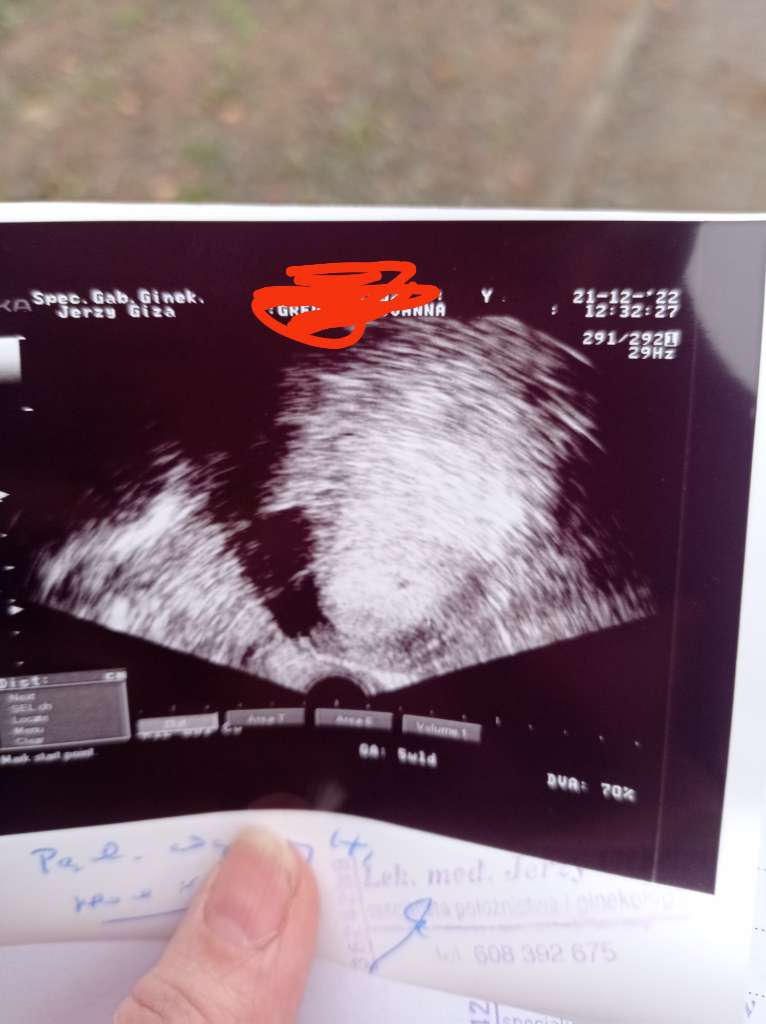

Ja od samego początku biorę tabletki (estrofem, encorton) pod język (luteina), dopochwowo (utrogestan) zastrzyki (prolutex, neoparin, accofil). Tylko po in vitro takie leki to najczesciej normaJest bobascałe 0,29cm. Z usg wyszło tyle samo co z OM czyli 5td6d. Echo zarodka też słyszałam! Minus taki że mam leżeć i pachnieć, się muszę oszczędzać. Dostałam multum leków min zastrzyki z heparyny, Dupasthon, Encorton, Utrogestan. Wizyta następna za 2 tyg z wynikami badań.

Super wiadomościJest bobascałe 0,29cm. Z usg wyszło tyle samo co z OM czyli 5td6d. Echo zarodka też słyszałam! Minus taki że mam leżeć i pachnieć, się muszę oszczędzać. Dostałam multum leków min zastrzyki z heparyny, Dupasthon, Encorton, Utrogestan. Wizyta następna za 2 tyg z wynikami badań.